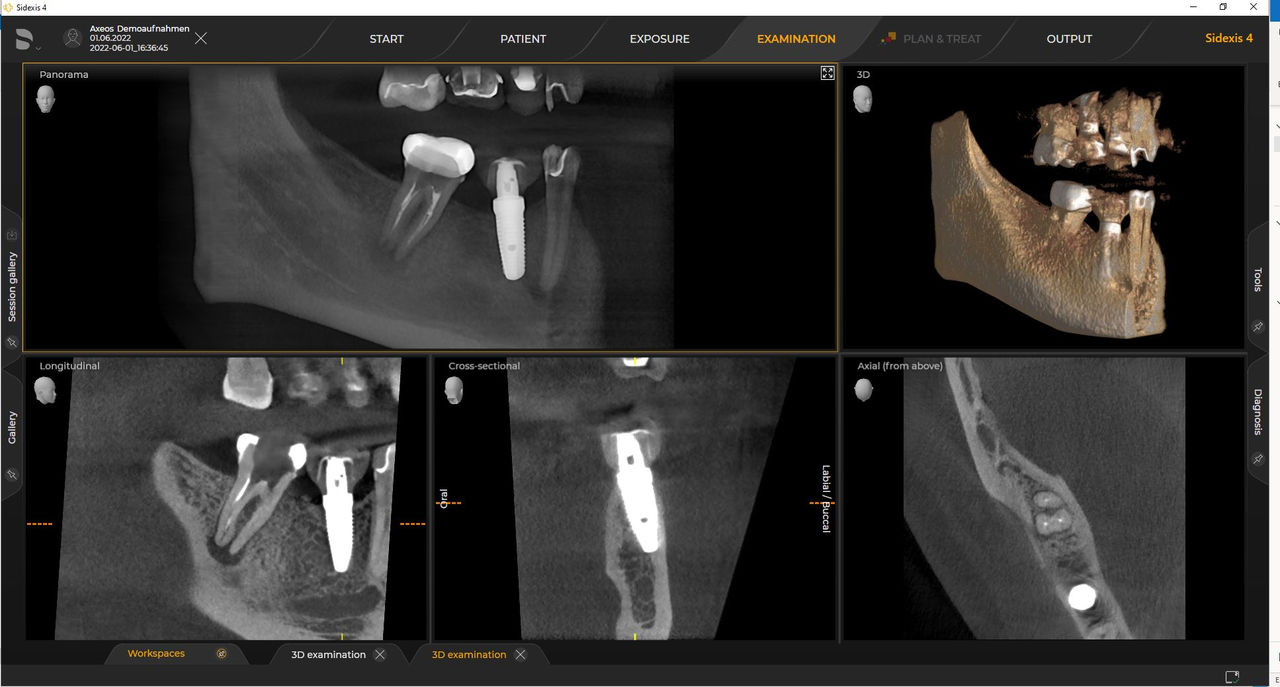

Numerous volume sizes ensure flexibility in everyday practice. Examine a precise area or evaluate the complete dentition including the TMJs

Thanks to the optimized low dose mode with a dedicated filter, the imaging of dense structures, such as bones, is possible at a greatly reduced dose. This makes Intelligent Low Dose an attractive and efficient option for many clinical situations. Whether in orthodontics or implantology - with Dentsply Sirona solutions you will find the optimum setting for every case.

Dentsply Sirona 3D units work exclusively with Sidexis 4. Nevertheless data migration from Sidexis XG to Sidexis 4 is very easy. Sidexis 4 allows for the full digital experience with the latest tools.